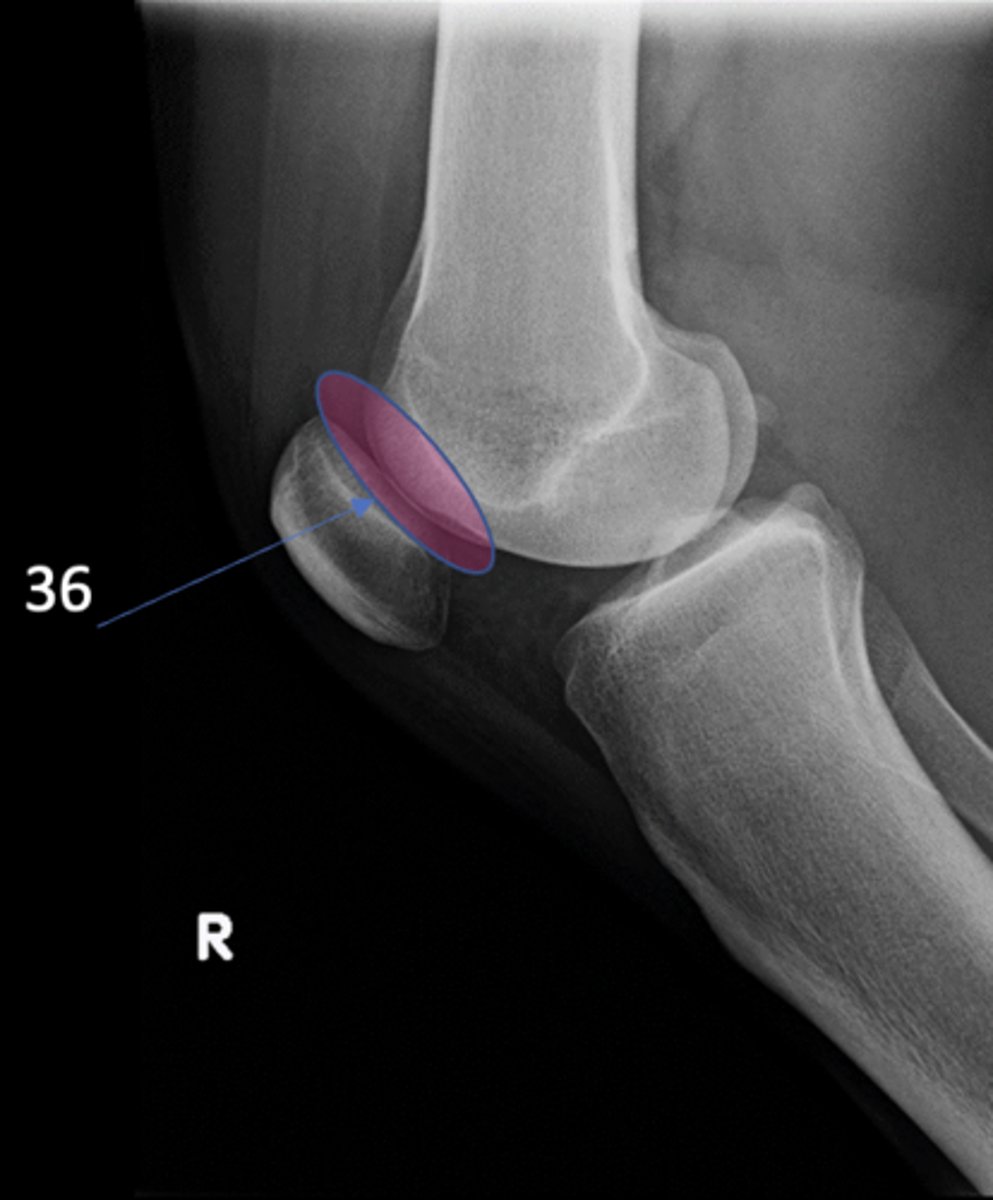

New cards

Patellofemoral joint

ID 36 (joint)

<p>ID 36 (joint)</p>

Ludloff's patch/spot

- Not a true anatomical structure

- Appears due to less bone being traversed anteriorly than posteriorly